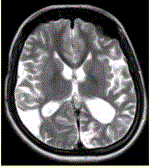

问题 女性,22岁。癫痫发作及智力异常。MRI显示见下图。 该病的诊断为

选项 A.海绵状血管瘤 B.发育性静脉畸形 C.AVM D.毛细血管扩张症 E.动脉瘤 F.硬脑膜动静脉漏 G.moyamoya

答案 G